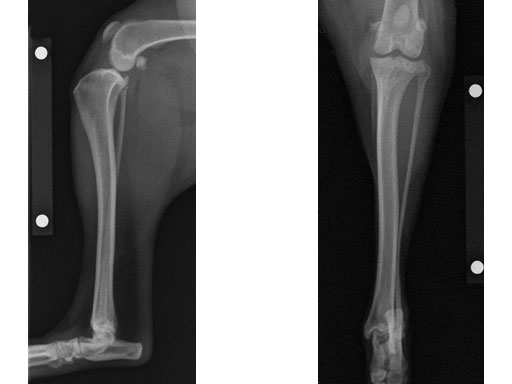

A four-year-old, female, spayed, 33 kg English bulldog had a CrCL tear and a medial patellar luxation. The small stature 3.5 mm TPLO plate was perfect for this dog due to the small profile of the bone and the need to use a heavier plate (3.5 vs a 2.7 mm). In the past, veterinary surgeons have been forced to either squeeze the standard TPLO 3.5 mm plate on the bone or use an undersized TPLO 2.7 mm plate. In this patient, the shorter and smaller profile head of the small stature TPLO 3.5 mm was perfect.